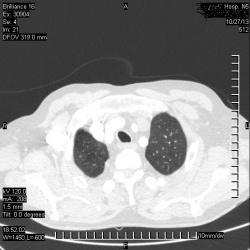

Прошу помощи!!! Коллеги!! Б-я 38лет- температура 37-38 два дня,6 дней –норма.При осмотре видны расширенные вены ПРАВОГО предплечья и ПРАВОГО плеча(с-м верхней полой вены????)На КТ-гр....

09.10.2010 - 11:39